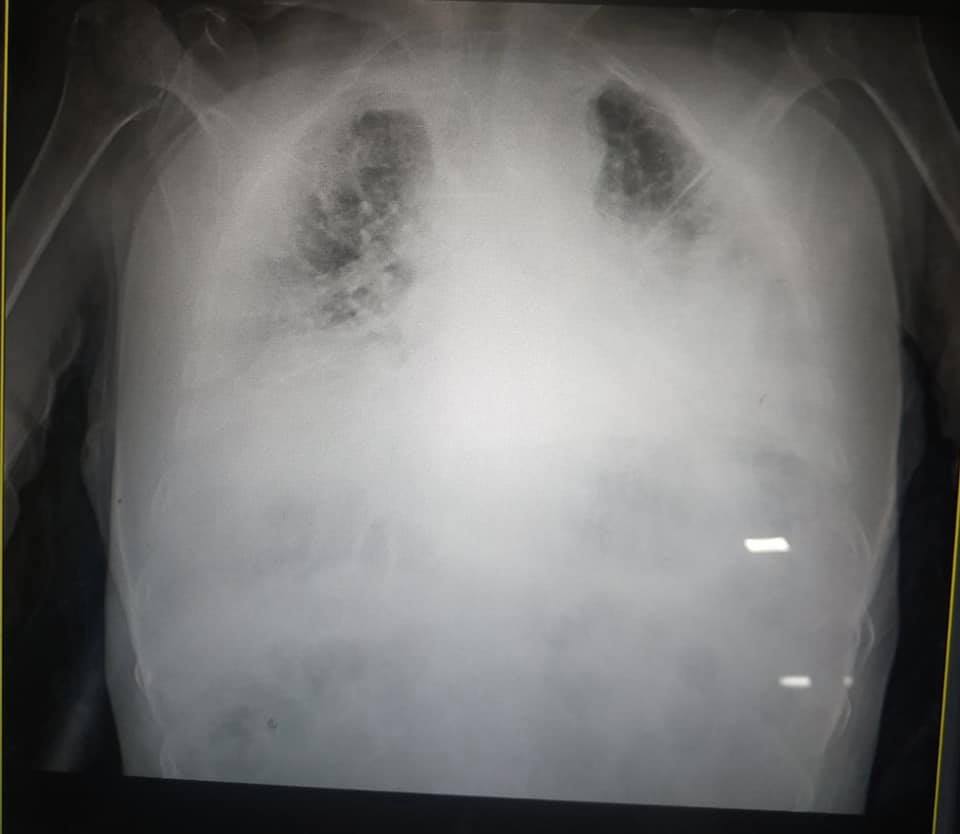

Больных действительно много. Немало и сложных случаев. На днях врачи поделились информацией о том, как же проходит лечение у таких больных. В частности, врач Львовской городской коммунальной больницы скорой помощи предоставила фото, где изображены пораженные коронавирусом легкие. Она добавила, что это самый тяжелый случай в ее практике, ведь легких почти нет - есть сплошное белое пятно. К слову, это медик, работает в больнице долго, и имеет большой опыт работы в этой сфере. Этим в социальной сети поделилась Иринa Зaслaвeц.

Такой жест сделано с целью достучаться до всех людей и помочь им понять, что COVID - на самом деле опасно и может творить страшные вещи в человеческом организме. Поэтому стоит беречь себя и родных от этого и придерживаться всех правил карантина.

Свой комментарий в рамках этой темы дал прoфeсoр Рoмaн Дyткa. По словам медика, во всех сложилось впечатление, что первое, что поражает COVID-19, являются легкие, однако это не так. Прежде всего коронавирус действует на сосуды и прежде всего поражает те, где много кислорода - это сосуды легких. Поэтому изменения в легких спровоцированы не пневмонией, а пневмонитом (патология сосудов), подчеркнул профессор. Именно поэтому всем больным COVID назначают препараты, которые разжижают кровь.